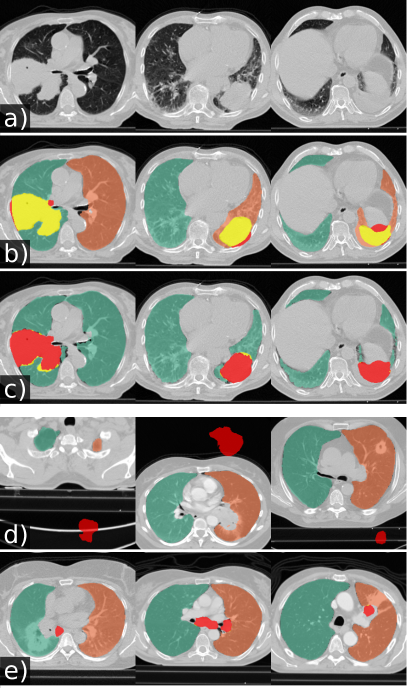

Models trained on routine data achieve improved evaluation scores compared to models trained on publicly available study data. U-net, ResU-net, and Deeplab v3+ models, when trained on routine data (R-36), yielded the best evaluation scores on the merged test dataset (All, n = 62). The U-net yields mean DSC, HD95, and MSD scores of 0.96 0.08, 9.19 18.15, 1.43 2.26 when trained on R-36 [U-net(R-36)] and 0.92 0.14, 13.04 19.04, 2.05 3.08 when trained on VISC-36 (R-36 versus VISC-36, p = 0.001, 0.046, 0.007) or 0.94 0.13, 11.09 22.9, 2.24 5.99 when trained on LTRC-36 (R-36 versus LTRC-36, p = 0.024, 0.174, 0.112). This advantage of routine data for training is also reflected in results using other combinations of model architecture and training data. Table III lists the evaluation results in detail. We determined that the influence of model architecture is marginal compared to the influence of training data. Specifically, the mean DSC does not vary for more than 0.02 when the same combination of training and test set was used for different architectures (Table III). Compared to readily available trained P-HNN model, the U-net trained on the R-231 routine dataset [U-net(R-231)] yielded mean DSC, HD95, and MSD scores of 0.98 0.03, 3.14 7.4, 0.62 0.93 versus 0.94 0.12, 16.8 36.57, 2.59 5.96 (p = 0.024, 0.004, 0.011) merged test dataset (All, n = 62). For comparison with the CIP-algorithm, only volumes for which the algorithm did not fail were considered. On the merged dataset (All, N=62) the algorithms yielded mean DSC, HD95, and MSD scores of 0.98 0.01 ,1.44 1.09 ,0.35 0.19 for the U-net(R213) compared to 0.96 0.05, 4.65 6.45, 0.91 1.09 for CIP (p = 0.001, 0.001, 0.001). Detailed results are given in Table IV. Fig. 2 shows qualitative results for cases from the routine test sets and Fig. 3 shows cases for which the masks generated by the U-net(R-231) model yielded low DSCs when compared to the ground truth. We created segmentations for the 55 cases of the LOLA11 challenge with the U-net(R-231) model. The unaltered masks yielded a mean overlap score of 0.968 and with dense areas removed 0.977. Table V and Fig. 4 show results for tumour overlap on the 318 volumes of the Lung1 dataset. U-net(R-231) covered more tumour volume mean/median compared to P-HNN (60%/69% versus 50%/44%, p 0.001) and CIP (34%/13%). Qualitative results for tumour cases for U-net(R-231) and P-HNN are show in Figs. 5b, c. We found that 23 cases of the Lung1 dataset had corrupted ground-truth annotation of the tumours (Fig. 5d). Fig. 5e shows cases with little or no tumour overlap achieved by U-net(R-231).

We showed that training data, sampled from the clinical routine, improves generalizability to a wide spectrum of pathologies compared to public datasets. We assume this lies in the fact that many publicly available datasets do not include dense pathologies such as severe fibrosis, tumour, or effusions as part of the lung segmentation. Further, they are often provided without guarantees about segmentation quality and consistency. While the Anatomy3 dataset underwent a thorough quality assessment, the organisers of the VESSEL12 dataset merely provided lung segmentations as a courtesy supplement for the task of vessel segmentation, and within the LCTSC dataset, “tumour is excluded in most data” and “collapsed lung may be excluded in some scans” [5]. Results indicate that that both, size and diversity of the training data, are relevant. State-of-the-art results can be achieved with images from only 36 patients which is in line with previous works [41] achieving a mean DSC of 0.99 on LTRC test data using the U-net(R-36) model. A large number of segmentation methods are proposed every year, often based on architectural modifications [31] of established models. Isensee et al. [31] showed that such modified design concepts do not improve, and occasionally even worsen, the performance of a well-designed baseline. They achieved state-of-the-art performance on multiple, publicly available segmentation challenges relying only on U-nets. This corresponds to our finding that architectural choice had a subordinate effect on performance. At the time of submission, the U-net(R-231) achieved the second highest score among all competitors in the LOLA11 challenge. In comparison, the first ranked method [22] achieved a score of 0.980 and a human reference segmentation achieved 0.984 [41]. Correspondingly, the U-net(R-231) model achieved improved evaluation measures (DSC, HD95, MSD and tumour overlap) compared to two public algorithms. There are limitations of our study that should be taken into account. Routine clinical data vary between sites. Thus, extraction of a diverse training dataset from clinical routine may only be an option for centres that are exposed to a wide range of patient variety. Evaluation results based on public datasets are not fully comparable. For example, the models trained on routine data compared to other datasets yielded lower performance in terms of DSC on the LCTSC test data. However, the lower scores for models trained on routine data in LCTSC can be attributed to the lack of very-dense pathologies in the ground truth masks. Fig. 3 illustrates cases for which the R-231 model yielded low DSC. The inclusion or exclusion of pathologies such as effusions into lung segmentations is a matter of definition and application. While pleural effusions (and pneumothorax) are technically outside the lung, they are assessed as part of lung assessment, and have a substantial impact on lung parenchyma appearance through compression artefacts. Neglecting such abnormalities would hamper automated lung assessment, as they are closely linked to lung function. In addition, lung masks that include pleural effusions greatly alleviate the task of effusion detection and quantification, thus making it possible to remove effusions from the lung segmentation as a post-processing step. We proposed a general lung segmentation algorithm relevant for automated tasks in which the diagnosis is not known beforehand. However, specialized algorithms for specific diseases could be beneficial in scenarios of analyzing cohorts, for which the disease is already known. In conclusion, we showed that accurate lung segmentation does not require complex methodology and that a proven deep-learning-based segmentation architecture yields state-of-the-art results once diverse (but not necessarily larger) training data are available. By comparing various datasets for training of the models, we illustrated the importance of training data diversity and showed that data from clinical routine can generalize well to unseen cohorts, highlighting the need for public datasets specifically curated for the task of lung segmentation. We draw the following conclusions: (1) translating ML approaches from bench to bedside can require the collection of diverse training data rather than methodological modifications; (2) current, publicly available study datasets do not meet these diversity requirements; and (3) generic, semantic, segmentation algorithms are adequate for the task of lung segmentation. A reliable, universal tool for lung segmentation is fundamentally important to foster research on severe lung diseases and to study routine clinical datasets. Thus, the trained model and inference code are made publicly available under the GPL-3.0 license to serve as an open science tool for research and development and as a publicly available baseline for lung segmentation under https://github.com/JoHof/lungmask.